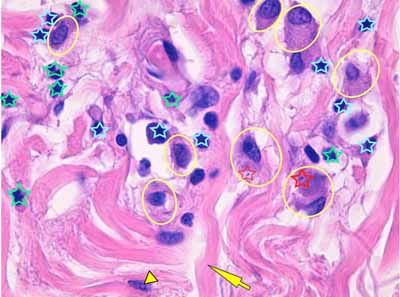

Photo 14 (Hémalun-Eosine X1000 objectif à immersion) : Vue au fort

grossissement de l’infiltrat inflammatoire dermique péri-vasculaire, formé de macrophages,

de plasmocytes et de granulocytes éosinophiles. Certains macrophages contiennent

un élément ovalaire de quelques micromètres de diamètre, discrètement bipolaire, dont

la silhouette apparaît compatible avec un parasite protozoaire et notamment avec le genre Leishmania.

Légendes de la Photo 14 :

- Étoile vertes : granulocytes éosinophiles

- Étoiles turquoises : plasmocytes

- Cercles jaunes : macrophages

- Pointe de flèche jaune : noyau de fibrocyte

- Flèche jaune : faisceau de fibres de collagène

- Étoiles rouges : un élément figuré est parfois visible dans le cytoplasme de macrophages, celui ciblé par l’étoile la plus épaisse apparaît nettement “bi-polaire” avec un pôle sombre (le noyau) et un pôle pâle (le cytoplasme) suggérant une forme amastigote de Leishmanie.